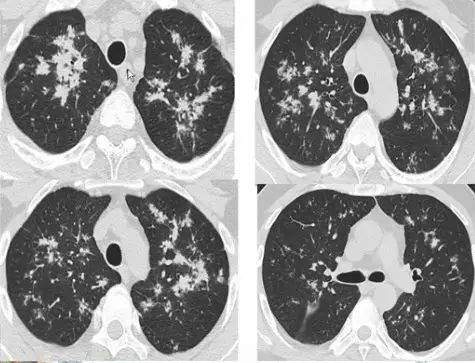

肺内“烟花征”,为活动性肺结核的CT表现之一。是结核经支气管播散并由多发小叶中央结节堆积而成,形态特征似烟花在空中散开。病理基础为细支气管及肺泡内干酪坏死性肉芽肿。